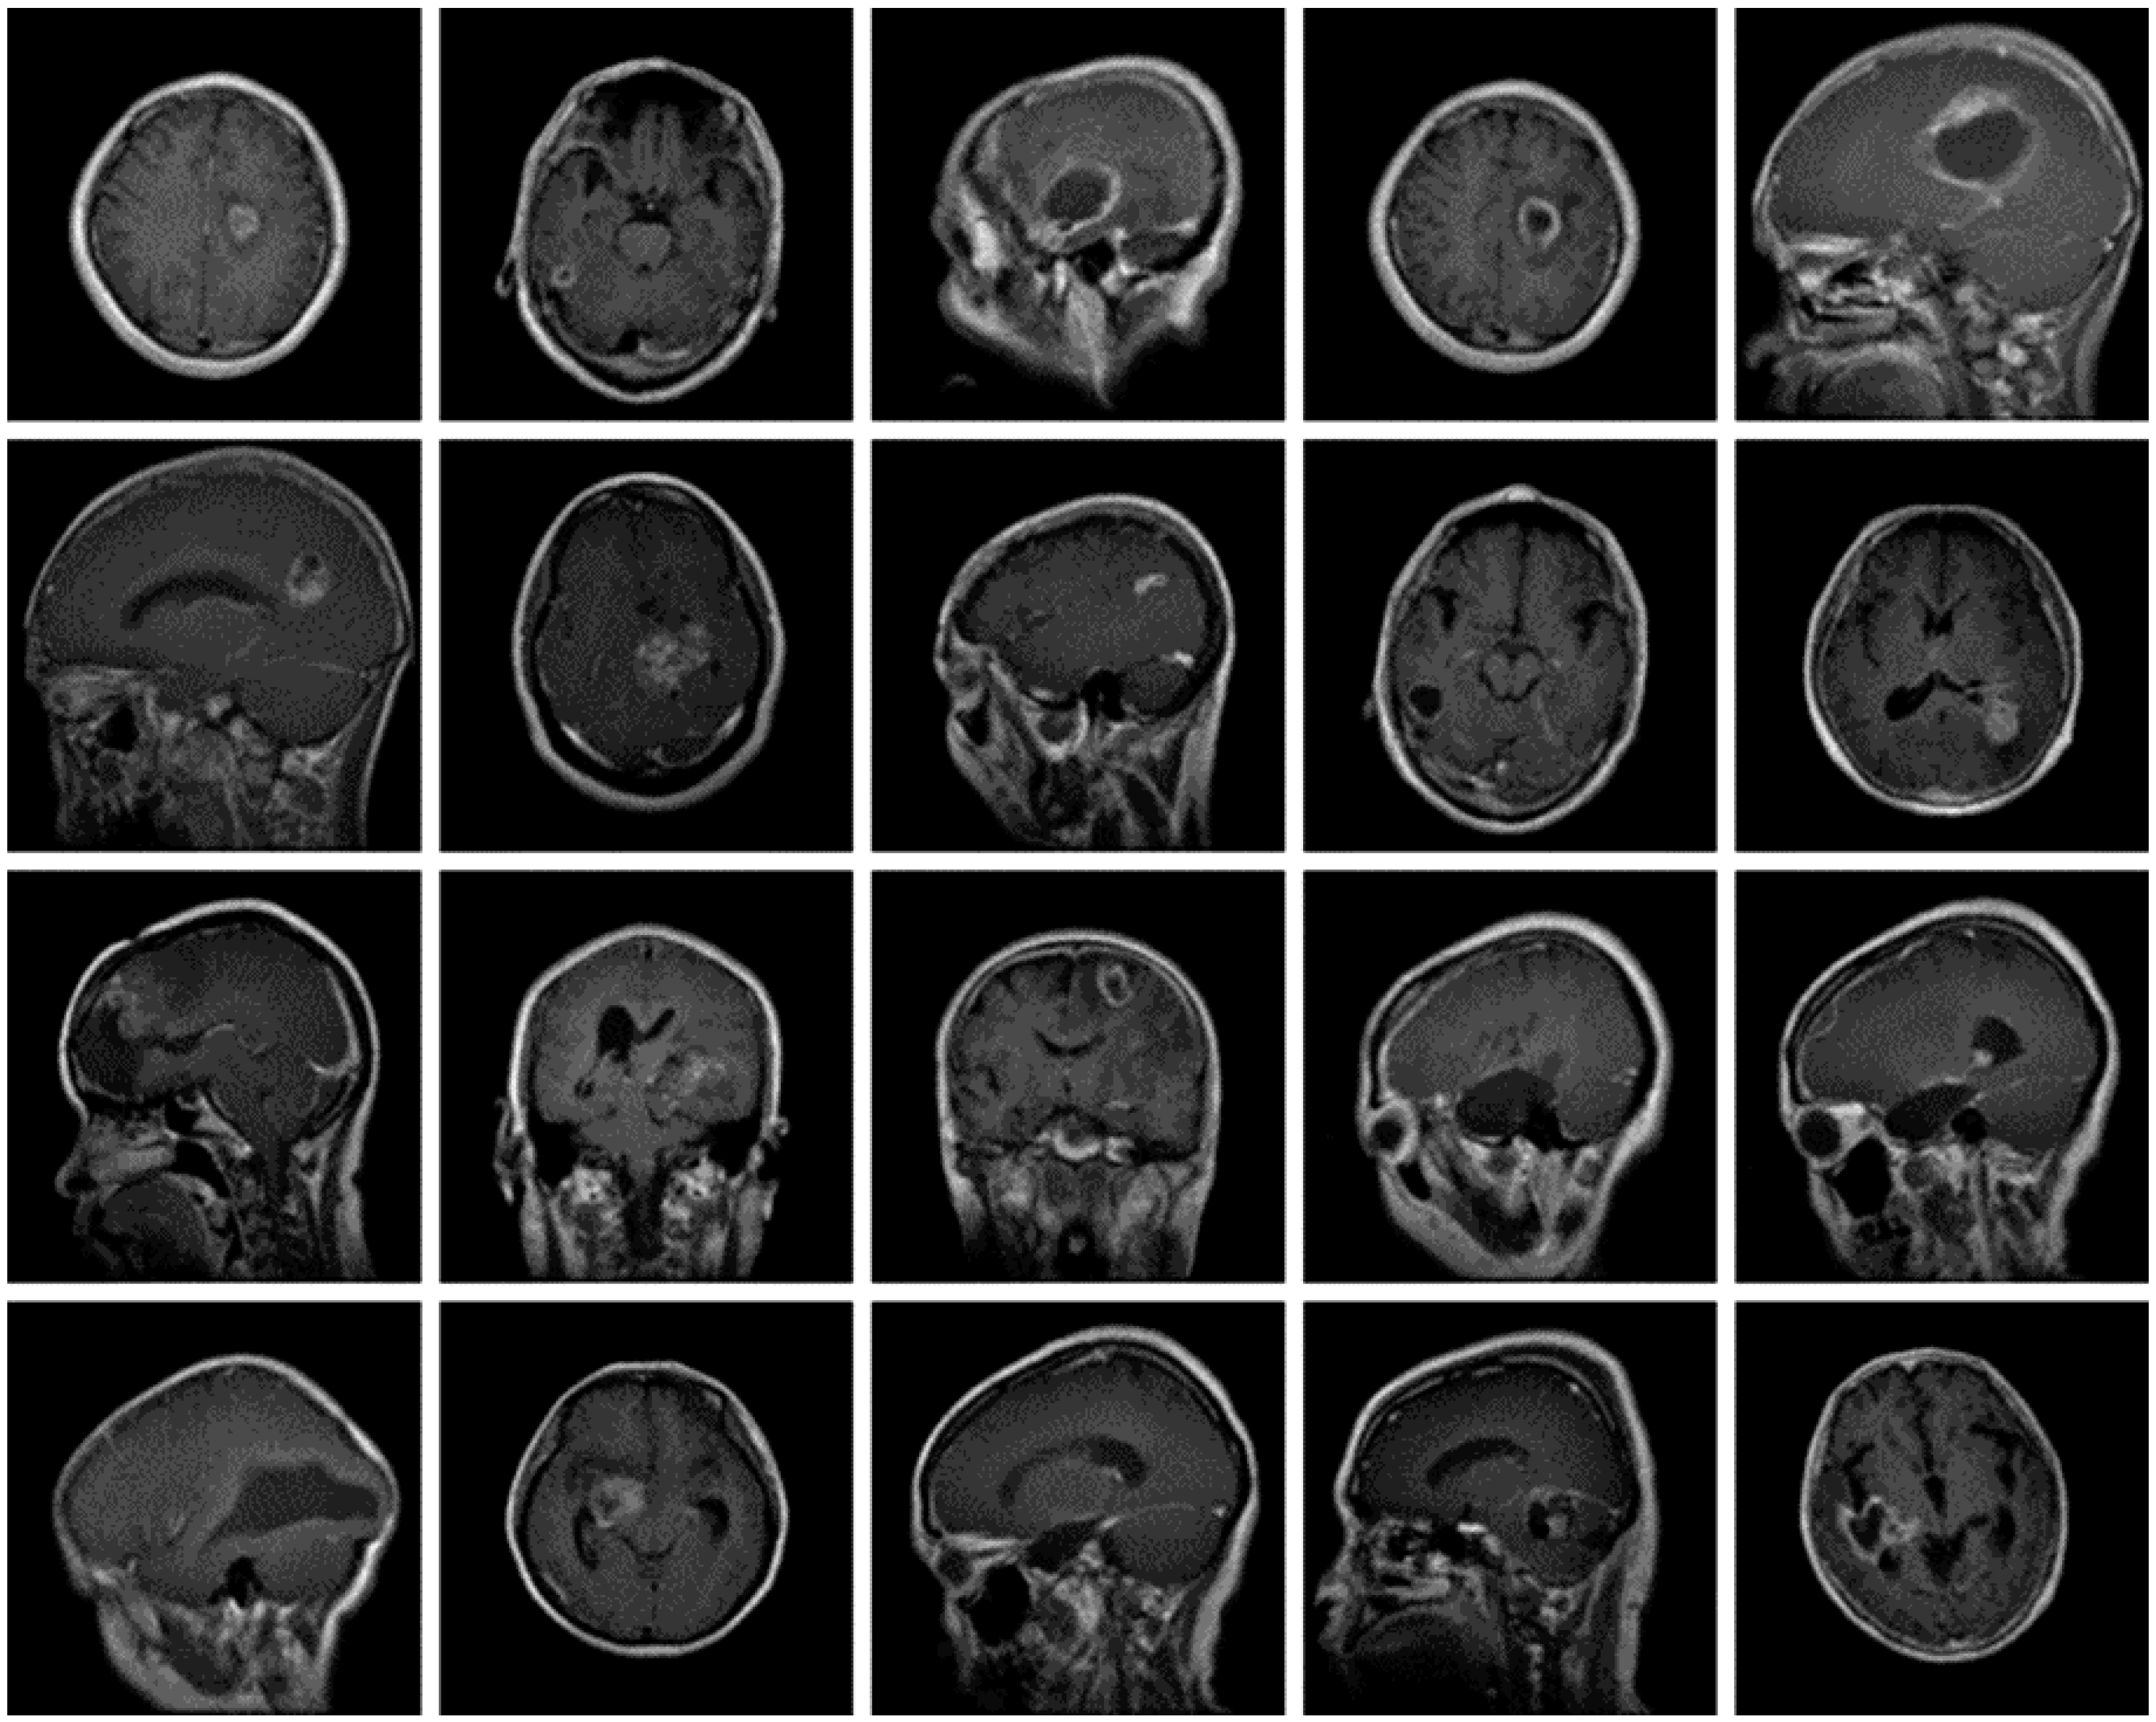

The dataset used for this current work is compiled from three other datasets: Figshare, SARTAJ, and Br35h. This composite dataset contains 2880 T1- weighted contrast-enhanced MRI brain images [26]. Gadolinium was used as contrast agent in these images. The target dataset has 829 images for glioma tumor, 825 images for meningioma tumor, 830 images for pituitary tumor and 396 images for no tumor cases. The images of the target dataset have a resolution of 512 × 512 × 3 with 24 bits color depth. Figure 1, Figure 2, Figure 3 and Figure 4 show some examples for each possible class: no tumor, glioma, meningioma, and pituitary tumor, respectively. The target dataset is split with 70% used for training and the remaining 30% kept aside for estimating the validation accuracy.

Figure 2.

Examples of MRI scans of Glioma tumors.